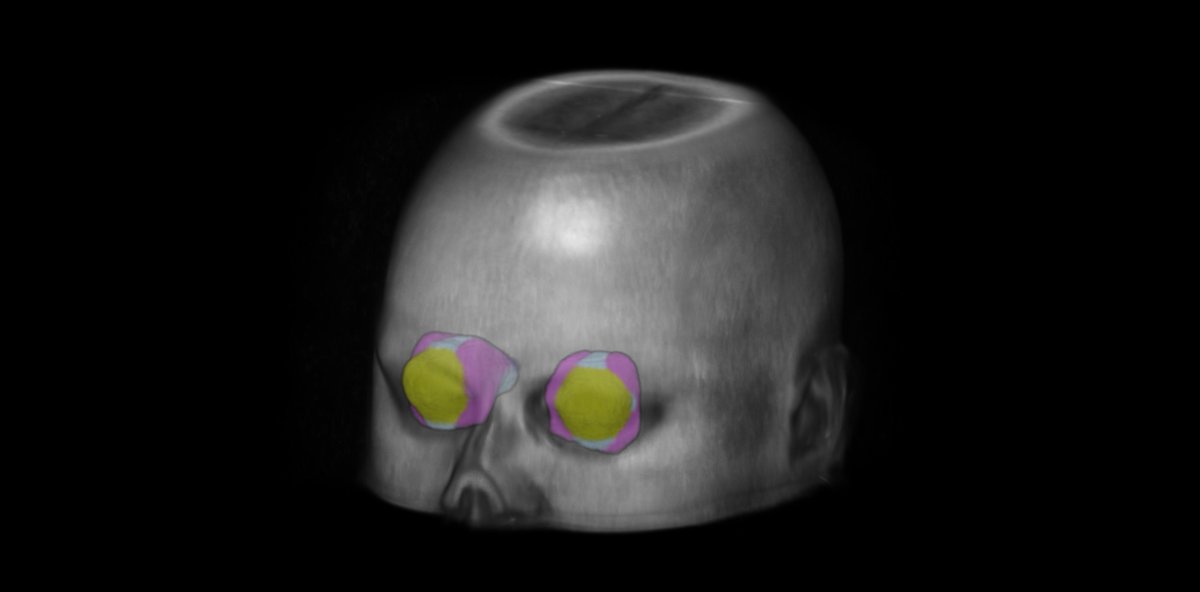

At the recent @vuiis Retreat, @AdamSaunders97 presented "Vasculature-informed spatial smoothing of white matter functional magnetic resonance imaging." This novel method smooths images along the vasculature to unlock insights into brain connectivity. @VanderbiltU